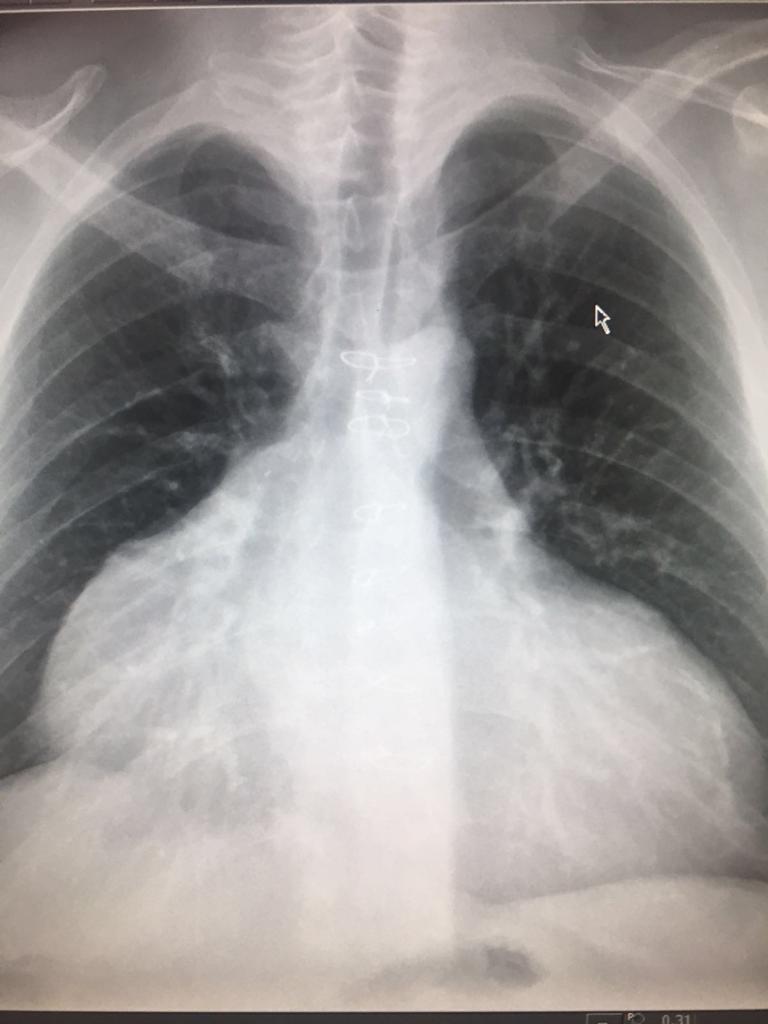

This one! The heterotopic or piggyback

This option was used in the past for patients with severe and/or fixed pulmonary hypertension and severe pulmonary vascular resistance in the absence of native right ventricular failure. Basically a primitive (and organic) VAD

Harefield has a handful of HHTx patients, many of them have survived 20+ years post-tx. They have their own particularities as you could imagine. Also, in our cohort, the anastomosis is donor PA to native RA to avoid the need to use prosthetic material